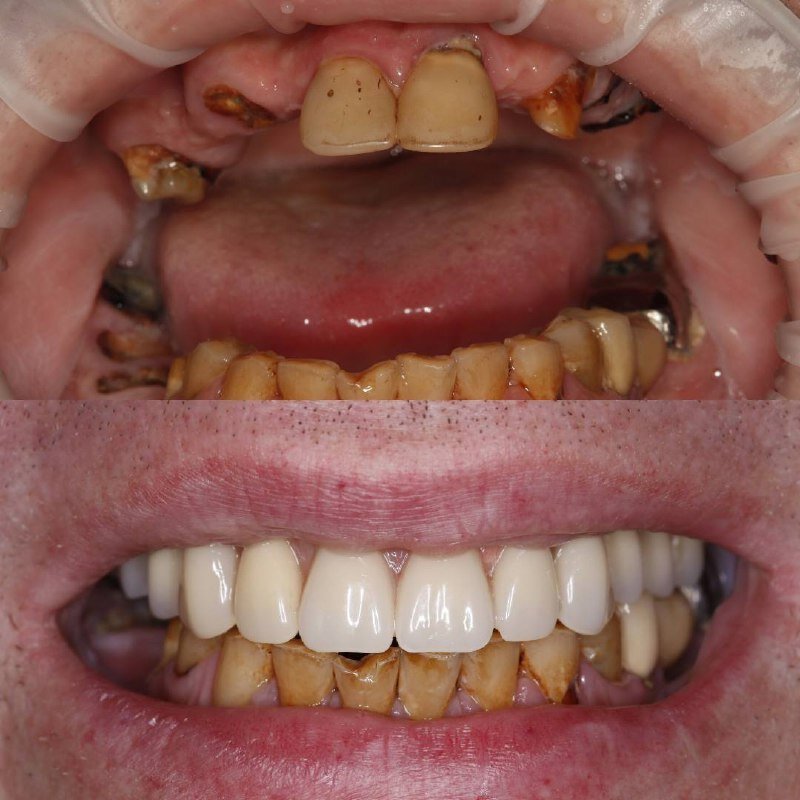

Фотогалерея

Если вы собираетесь добиться сияющей улыбки, то работу над ней лучше доверить экспертам. В стоматологической клинике Династия Н имеется специализированное оборудование для того, чтобы ваши зубы снова стали белоснежными. В нашей стоматологии оказывают услуги лечения кариеса, удаления зубов, компьютерной томографии, отбеливания, исправления прикуса, рентгенологической диагностики, изготовления имплантов, а также установки металлокерамики, брекетов, имплантов, виниров. С нами ваша улыбка будет яркой, а зубы крепкими!

Делает протезирование на имплантатах, в том числе all-on-4 и all-on-6.